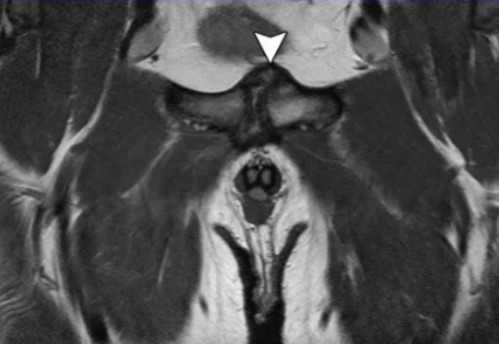

МРТ: симфизит, стрелка указывает на утолщение капсулы, неровность контуров